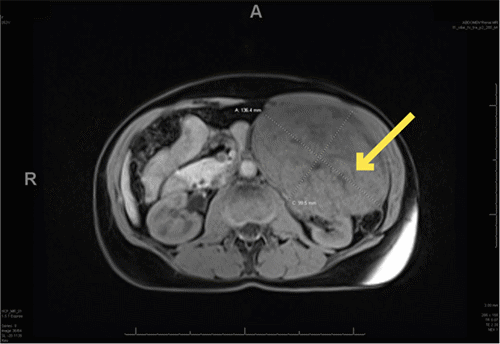

The patient was referred to the surgical oncology service for preoperative evaluation and operative planning for the excision of the mass. Given the size and symptomatic nature of the mass, a decision was made to pursue a more radical surgical excision instead of a percutaneous biopsy. Preoperative computed tomography of the abdomen and pelvis was obtained to assess the anatomic planes for resection because the MRI images performed at the previous medical facility were not readily available (Figure 2).

Figure 2. CT with IV Contrast Images of Mass. Published with Permission

A) Axial at its largest dimensions; images were used for preoperative planning and visualization of planes of dissection

B) Coronal at its largest dimensions; images were used for preoperative planning and visualization of planes of dissection